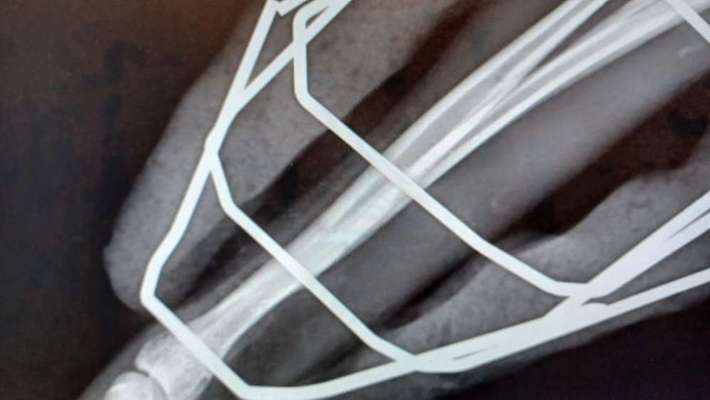

Lucy hat sich das Vorderbein gebrochen. Ein unkomplizierter Bruch der Speiche. Gestern wurde bei ihr ein Fixateur extern montiert. In 2-3 Tagen kann sie nach Hause. Der Fixateur soll etwa 6 Wochen dran bleiben. EDIT: Ich habe 2 Fotos und Röntgenbilder ergänzt, damit man eine Vorstellung hat, wie so etwas aussehen kann. Wenn wir sie abholen, bekommen wir natürlich noch genauere Infos vom Arzt, was wir beachten müssen. Trotzdem fragen wir uns jetzt schon, wie wir damit im Alltag umgehen sollen. Hat jemand Erfahrungen mit einem Fixateur extern? Was ging damit gut, was ging nicht? Was hat Euch überrascht? Wir sind für jegliche Informationen dankbar. EDIT: Hier noch mal die Eckdaten: 29.07.2023 Lucy bricht sich das Vorderbein 30.07.2023 In der Tierklinik wird das Bein mit einem externen Fixateur stabilisiert 02.08.2023 Lucy wird aus der Klinik entlassen Bis zu 10 Minuten am Stück gehen, nicht Springen, Toben, Rennen Ab 18.09.2023 ist bis zu 30 Minuten am Stück gehen erlaubt 2x Entzündung an den Pinnen des Fixateurs 3x Kontrollröntgen 25.10.2023 Der Fixateur wird in der Klinik entfernt Das Bein wird durch einen Verband geschützt und stabilisiert, der alle 2 - 3 Tage beim Tierarzt gewechselt wird Bis zu 10 Minuten am Stück gehen, nicht Springen, Toben, Rennen 02.11.2023 Der Verband ist ab 07.11.2023 kein Kragen mehr nötig

Hier sind die Röntgenbilder vom 18.9.23

Man sieht, dass sich da schon viel getan hat, und dass der Knochen gerade zusammen wächst. Aber es ist auch deutlich zu sehen, dass noch Substanz fehlt.

Wir hoffen nun auf das Kontrollröntgen am 16.10.